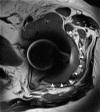

Results: All patients presented with pain or swelling around the hip, and two patients presented with recurrent instability. Serum cobalt levels were elevated prior to the revision arthroplasty and were typically more elevated than were serum chromium levels. Surgical findings included large soft-tissue masses and surrounding tissue damage with visible corrosion at the femoral head-neck junction; the two patients who presented with instability had severe damage to the hip abductor musculature. Pathology specimens consistently demonstrated areas of tissue necrosis. The patients were treated with debridement and a femoral head and liner exchange, with use of a ceramic femoral head with a titanium sleeve in eight cases. The mean Harris hip score improved from 58.1 points preoperatively to 89.7 points at a mean of 13.0 months after the revision surgery (p=0.01). Repeat serum cobalt levels, measured in six patients at a mean of 8.0 months following revision, decreased to a mean of 1.61 ng/mL, and chromium levels were similar to prerevision levels. One patient with moderate hip abductor muscle necrosis developed recurrent instability after revision and required a second revision arthroplasty.